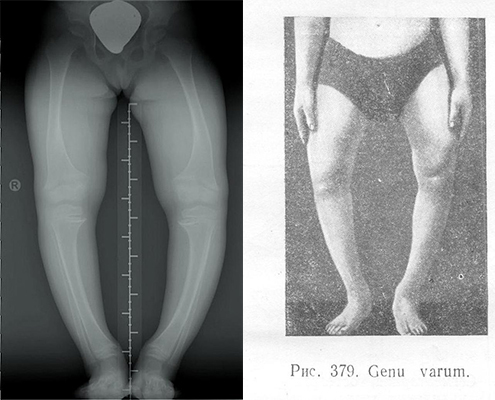

Рекурвация коленного сустава: рентгеновские снимки и объяснения